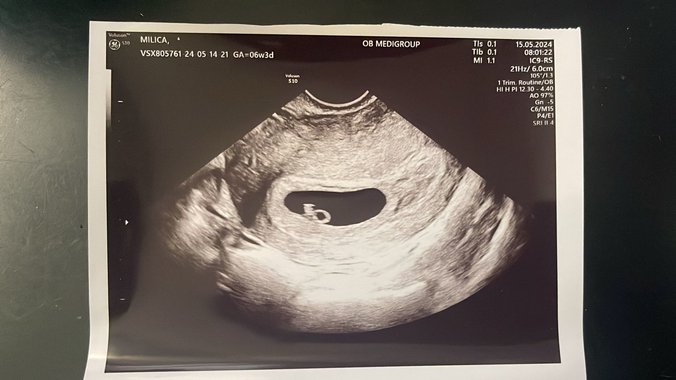

Ona je danas obavila i ginekološki pregled. Saznala je da je trudna već 6 nedelja, a portal Pink.rs dobio je i snimak sa ultrazvuka!

Foto: Pink.rs